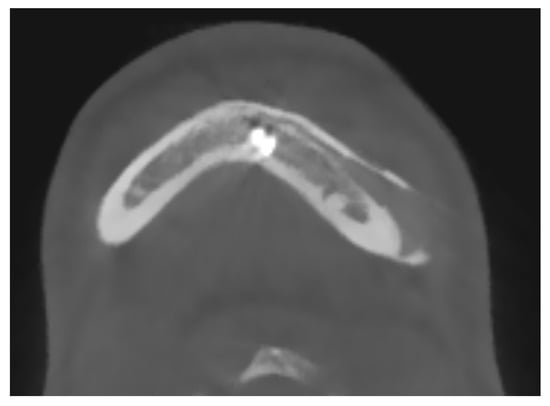

The case of maxillofacial surgery where bone regrowth was not observable underscores the importance of a sufficient bone–prosthesis interface for a successful osteointegration (see Figure 3). The neurosurgical case series, in which the interface between bone and prosthesis for cranioplasty is minimal, further corroborated this statement. Studies have shown that a larger contact area between the implant and bone facilitates osteoblastic activity and bone ingrowth [47]. In addition, implants with roughened surfaces or porous coatings promote greater bone ingrowth compared to smooth-surfaced implants [48,49]. For this reason, factory-created holes are a valuable aid in the creation of bone tissue within them, as demonstrated in the previously analyzed case. Other studies aimed at enhancing the bioactivity of PEEK to improve the bone–implant interface are still in the in vitro stage, but we anticipate significant progress soon [50,51].

Figure 3.

The maxillo-facial surgery case representing the absence of ossification, caused by poor interface between bone and prosthesis.